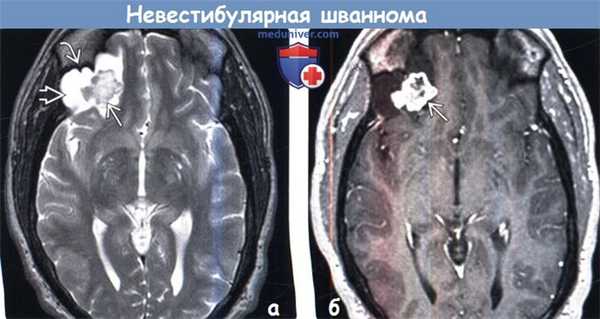

(а) MPT, Т2-ВИ, аксиальный срез: в нижнем отделе правой лобной доли определяется кистозное объемное образование с пристеночным солидным компонентом.

Обратите внимание на доброкачественное ремоделирование (с формированием фестончатости) прилежащих костей свода черепа, что говорит о медленном типе роста объемного образования.

(б) МРТ, постконтрастное Т1-ВИ, аксиальный срез: определяется интенсивное контрастирование пристеночного солидного компонента опухоли.

Большинство внутричерепных шванном имеют внемозговую локализацию и связь с черепными нервами. Паренхиматозные шванномы встречаются редко ( < 1% шванном), часто имеют вид кисты с пристеночным солидным компонентом.